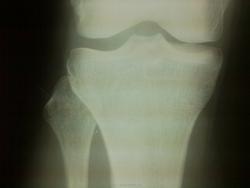

Ничего травматического в костях вроде не видно. М.б. надколенник, но и тут по Катону 1.

Костных повреждений не вижу.

Подчеркну: РЕНТГЕНОЛОГИЧЕСКИ хорошо. Хотя, оценить величину пателло-феморальной щели без снимка другого колена не представляется возможным.

В большеберцовой кости есть изменения, вероятно перелом...

Возможно, минимальная импрессия медиального мыщелка большеберцовой?..